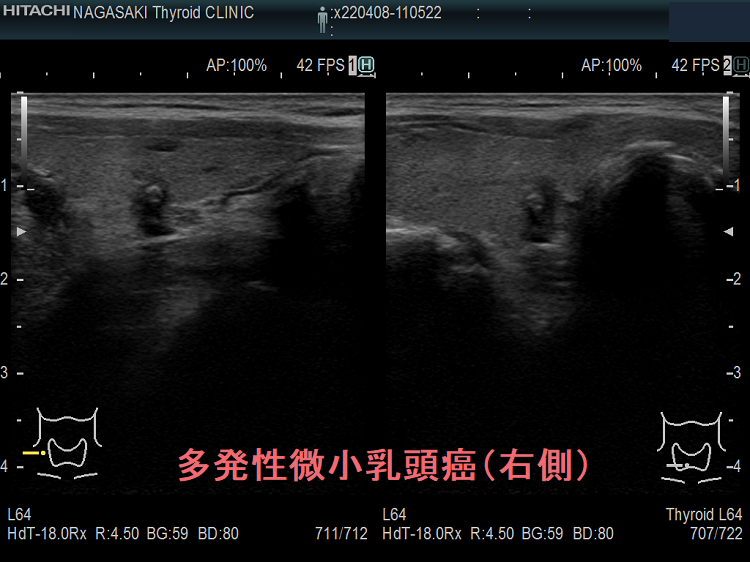

多発性の甲状腺微小乳頭癌

多発性の甲状腺微小乳頭癌は、リンパ節転移しやすいとされます(Am J Surg. 2014 Sep;208(3):412-8.)。

- 海外では、①両葉多発性の場合、②甲状腺癌の家族歴(遺伝性)がある場合、甲状腺微小乳頭癌であっても甲状腺全摘が推奨されます[アメリカ甲状腺学会(American Thyroid Association:ATA)やヨーロッパ分子癌学会(European Society of Molecular Oncology:SMO)のガイドライン](Thyroid. 2016 Jan;26(1):1-133.)(Ann Oncol. 2019 Dec 1;30(12):1856-1883.)(下記)

一方、隈病院の見解では、両葉多発性、甲状腺癌の家族歴(遺伝性)があっても、通常の甲状腺微小乳頭癌と同じ扱いとのです(Eur J Surg Oncol. 2018 Mar;44(3):307-315.)